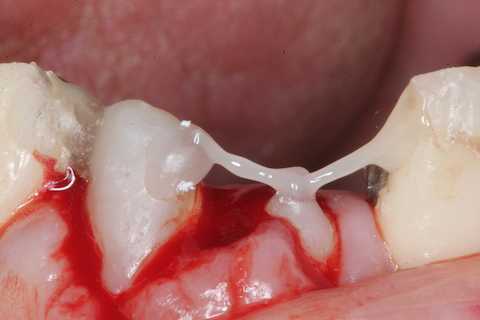

あとは接着固定しながら、歯冠を再建していく。